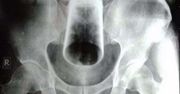

Zadzierzgnięcie jelita - przyczyny, objawy, diagnostyka, leczenie